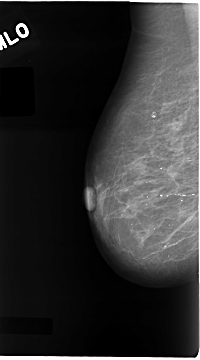

C_0111_1.RIGHT_MLO

RIGHT_MLO LINES 4680 PIXELS_PER_LINE 2592 BITS_PER_PIXEL 12 RESOLUTION 50 NON_OVERLAY